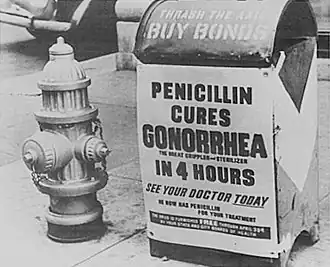

Antibiotics are used to treat gonorrhea infections. As of 2016, both ceftriaxone by injection and azithromycin by mouth are most effective.[4][57][58][59] However, due to increasing rates of antibiotic resistance, local susceptibility patterns must be taken into account when deciding on treatment.[36][60] Ertapenem is a potential effective alternative treatment for ceftriaxone-resistant gonorrhea.[61][62]

Antibiotic resistance

Many antibiotics that were once effective including penicillin, tetracycline, and fluoroquinolones are no longer recommended because of high rates of resistance.[36] Resistance to cefixime has reached a level such that it is no longer recommended as a first-line agent in the United States, and if it is used a person should be tested again after a week to determine whether the infection still persists.[57] Public health officials are concerned that an emerging pattern of resistance may predict a global epidemic.[67][68] In 2016, the WHO published new guidelines for treatment, stating "There is an urgent need to update treatment recommendations for gonococcal infections to respond to changing antimicrobial resistance (AMR) patterns of N. gonorrhoeae. High-level resistance to previously recommended quinolones is widespread and decreased susceptibility to the extended-spectrum (third-generation) cephalosporins, another recommended first-line treatment in the 2003 guidelines, is increasing and several countries have reported treatment failures."[69]